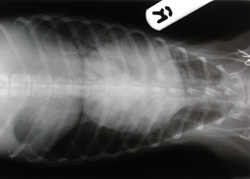

X RAY REF: 20 DATE: 8/10/99

SPECIES: DOG BREED: YORKIE

OWNER: BLOWES ANIMAL: MAX

AGE: 12 YEARS SEX: MALE

WEIGHT: 4.3 KG BUILD: AVERAGE

Max had been on long term treatment for a grade VI heart murmur for 1 year, with frusemide 20 mg tablets quarter daily and lanoxin 0.0625 mg tablets half twice daily. He was stable on the medication and doing well. Then he was bitten by a dog and suffered a glenoid fracture of the right scapula. This was repaired and postoperatively the dog was doing well. Two months later the owner presented Max for coughing and wheezing which had been getting progressively worse for the last 3 weeks. Max was booked in for radiography and ultrasonography, the owner having signed a consent form for the procedures and general anaesthesia. The dog was starved from the night before with access to water until 2 hours prior to premedication.

The forelegs are drawn well forward, out of the cranial thoracic field. There is a little axial rotation which can be seen where the ends of the ribs are not in alignment. Perhaps more time spent assessing the elevation of the sternum could have improved this. However, this dog had a barrel shaped thorax which makes visual assessment difficult.

Dorsoventral

Good collimation is necessary for both film quality and personnel safety. All 4 film edges are unexposed which demonstrates the extent of the primary beam. Close collimation is required to reduce scatter from tissues which are not under investigation. This scatter will reduce the overall quality of the radiograph's detail. Both of these projections are collimated reasonably well. Both are collimated correctly, just cranial to the manubrium and to the last rib. Laterally the collimation is acceptable on the dorsoventral projection, and dorsally on the lateral projection the collimation is correct, as it is important to see the dorsocaudal lung fields.

Exposure

The exposure of these projections is reasonable. The thorax can be a difficult area to obtain good overall exposure. The lungs having a very low physical density and the heart having a high physical density. Therefore one or other organ will be under or overexposed. For this reason a high kV and low mAs are used - higher kV's produce less contrast between different physical densities of tissues. The other advantage of this technique is that exposure times can be shorter which helps with the problem of movement blur that occurs when radiographing the thorax. There is a large range of densities on both projections, and the definition (sharpness is reasonable). With regard to detail, the pulmonary vessels can be seen and the caudal vena cava is visible on the lateral projection. The aorta is not visible but that may be due to the heart enlargement.

On the dorsoventral projection the heart is well penetrated, allowing site of the bifurcation of the trachea (carina) at the level of T5 and the bronchi. Detail could be better with regard to the internal structures of the lungs. Perhaps manual inflation of the lungs to maintain maximum lung expansion without respiratory movement whilst the exposure is made might have improved detail. This is not possible at this practice, as no one is allowed in the room whilst an exposure is made.

The lateral projection was taken on inspiration. The caudal crura meet the vertebral column at T13. On inspiration there should also be a space between the heart and diaphragm. However, as this radiograph demonstrates, if the heart is enlarged it is not a reliable indicator of the respiratory cycle.

Diagnosis

The radiography enabled the size of the cardiac shadow to be assessed - in this case it is grossly enlarged. Pulmonary oedema was also seen within the lungs. With the results of both radiography and ultrasonography the treatment regime was changed to frusemide 40mg quarter twice daily, lanoxin pg 0.25 mls per os twice daily and Cardiovet 5mg quarter twice daily for 2 days then half twice daily.

In this case a complete diagnosis could not be made with radiography. Ultrasonography was also used prior to general anaesthesia to assess the physical condition of the heart. The results of which showed - a massive volume overload of the left atria and ventricle. The mitral valve is thickened and can actually be seen leaking when fully closed. See figure 1.